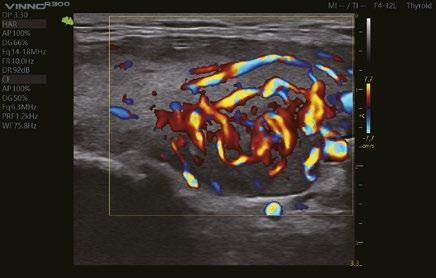

Erkennung der Fließgeschwindigkeit des Blutes. Es ermöglicht eine feinere Diagnose, bei besonders schwierigen Untersuchungen des Blutflusses.

Eine innovative Technologie, die die Visualisierung des Blutflusses verbessert, indem sie eine 3D-Darstellung der Farb-/Power-Doppler-Bildgebung anzeigt.